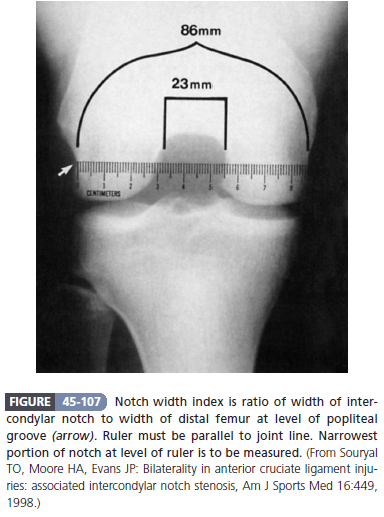

Intercôndilo estreito. Largura do intercôndilo/largura dos côndilos (medidos na altura do sulco do poplíteo): valor de referência 0,231+-0,044. Atletas com > 1 desvio padrão abaixo da média apresentam maior chance de rotura do LCA.